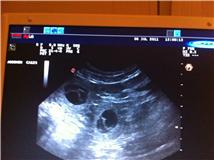

Bilder fra Ultralyd 6/7-2011:

Her ser du to.

Dette er en noe usikker metode for å vite hvor mange valper det er, men vet i hvertfall at hun er drektig. Vi kunne telle fem valper, men det er veldig usikkert. Det kan være flere eller færre. Tiden vil vise.